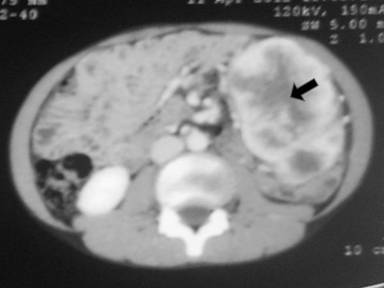

A 11-year-old male presented with complaints of painless hard swelling involving left lumber, umbilical and left hypochondrium of abdomen. According to his mother he was apparently asymptomatic 20 days back when he incidentally noticed firm to hard swelling in left upper abdomen. No history of fever, vomiting, jaundice, weight loss and hematemesis and bleeding per rectum was seen. No family history of a genetic disease was seen. Clinical examination was normal. Body fluid amylase was 4,800 U/L (reference range: 4-234 U/L) and liver function tests were normal. Computed tomography (CT) revealed a large mass measuring 10.0x8.8x7.5 cm in the pancreatic tail, mainly solid but small cystic component (Figure 1). The pancreatic tail mass was well-delimited but not encapsulated. There was no evidence of local invasion or metastasis. The surrounding vessels (celiac trunk, superior mesenteric artery, and splenic and portal veins) were not invaded. The surrounding pancreas was normal. The clinical diagnosis of adenocarcinoma of the pancreas was suspected. Resection of pancreatic tail mass and distal pancreatectomy with splenectomy was performed. Operative findings showed a mass with cyst involving pancreatic tail, adherent to splenic vein and artery, free from stomach and left kidney. The macroscopic examination revealed compressed pancreas measuring 4.0x1.0x0.5 cm, spleen measuring 8.5x6.0x3.5 cm with mesentery measuring 3.0x3.0x0.5 cm. and a well circumscribed, non-encapsulated, dense, mesenchymal tumor measuring 10.0x8.8x7.5 cm with a cystic area measuring 1.5 cm in diameter (Figure 2). Outer surface of the tumor was grey white and lobulated. No lymph node was seen. Histological examination showed a circumscribed tumor arranged in intersecting fascicles infiltrated the surrounding pancreatic parenchyma (Figure 3).Tumor cells are mildly anisomorphal with spindle shaped cells having elongated nuclei with blunt ends and bipolar cytoplasm. Mitosis is infrequent (less than 1-2 per 10 high power fields). Necrosis was not seen. Spindle shaped cells have a regular nucleus and were separated by large amounts of collagen fibers in edematous tissue with some inflammatory cells (Figure 4). The cystic component was seen within the tumor. Spleen showed congestion and focal fibrosis. Immunohistochemical analysis revealed that the tumor cells were strongly positive for beta-catenin (Figure 5), vimentin (Figure 6) and negative for cytokeratin (CK), CD34 (Figure 7), S100, CD68, CD117, smooth muscle actin (SMA) (Figure 8), muscle specific actin, desmin, CD99, Bcl2, anaplastic lymphoma kinase 1 (ALK-1) and human melanoma vlack 45. Proliferation marker Ki67 stained about 2% of the tumor cells. The immunohistochemistry and histopathological features were consistent with a confirmed diagnosis of desmoid tumor. A short term follow-up showed rapid disappearance of the symptoms which had revealed the desmoid tumor. Because of complete resection and the sporadic origin of the desmoid tumors, no corresponding treatment was given. After 10 months of follow-up, the patient is well and normal on clinical examination.

Figure 1. Computed tomography revealed a large mass (10.0x8.8x7.5 cm) in the pancreatic tail, mainly solid but with some cystic component (arrow). |